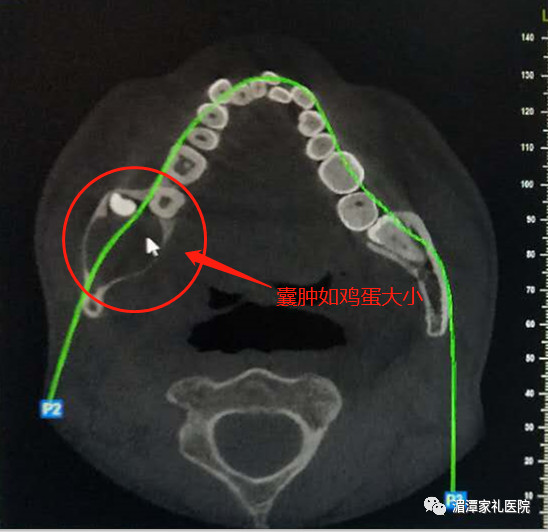

口腔主任胡云仔细检查后诊断,患者“右下颌角下颌支含齿囊肿”。

患者术前口腔颌面部全景CT

摘除后的囊肿如鸡蛋般大小